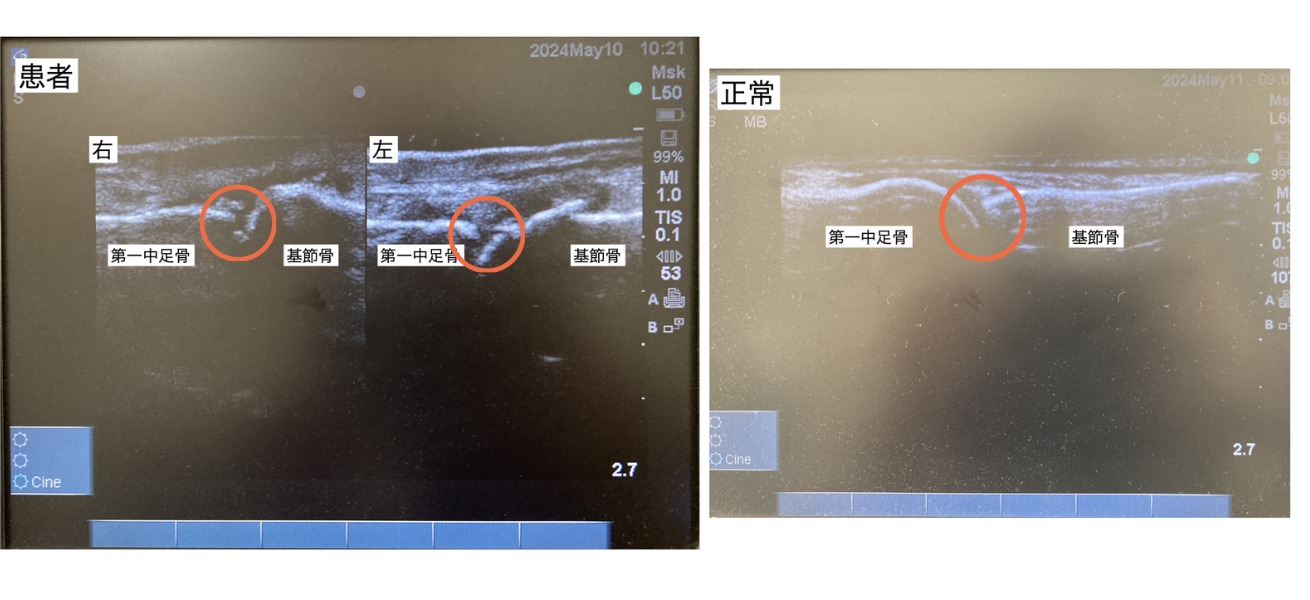

外反母趾

モートン病